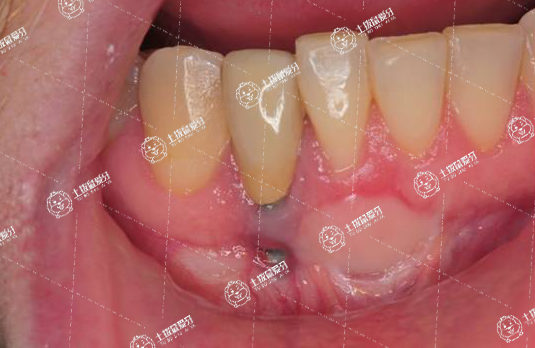

牙齒矯正牙齒松動(dòng)

矯正過(guò)程中牙齒從一個(gè)舊的位置移到一個(gè)新的位置,多多少少會(huì)存在一些松動(dòng),這種情況不需要過(guò)于擔(dān)心,因?yàn)槌C正結(jié)束以后都可以恢復(fù)。

但臨床上可能會(huì)碰到松動(dòng)度比較嚴(yán)重的,如牙齒移動(dòng)速度不一樣時(shí)可能跟對(duì)頜牙形成一些咬合創(chuàng)傷,這種創(chuàng)傷存在后牙齒松動(dòng)度會(huì)加重,此時(shí)需要及時(shí)找主診醫(yī)師,把咬合創(chuàng)傷的具體點(diǎn)調(diào)磨,進(jìn)行相應(yīng)處理。

另外臨床中醫(yī)生加力時(shí)力量過(guò)大也可導(dǎo)致牙齒松動(dòng)度比較明顯,此時(shí)也需要進(jìn)行一些相應(yīng)調(diào)整。